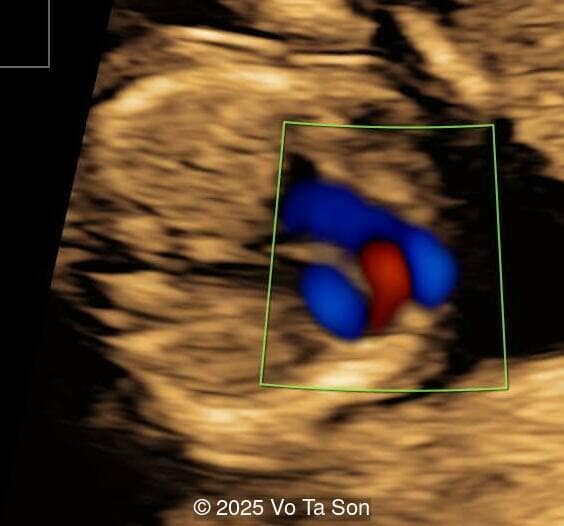

Spinal defect in the sacral region visualized on 3D ultrasound.

Image 3 Spinal defect in the sacral region visualized on 3D ultrasound.

Image 4 Spinal defect in the sacral region visualized on 3D ultrasound.